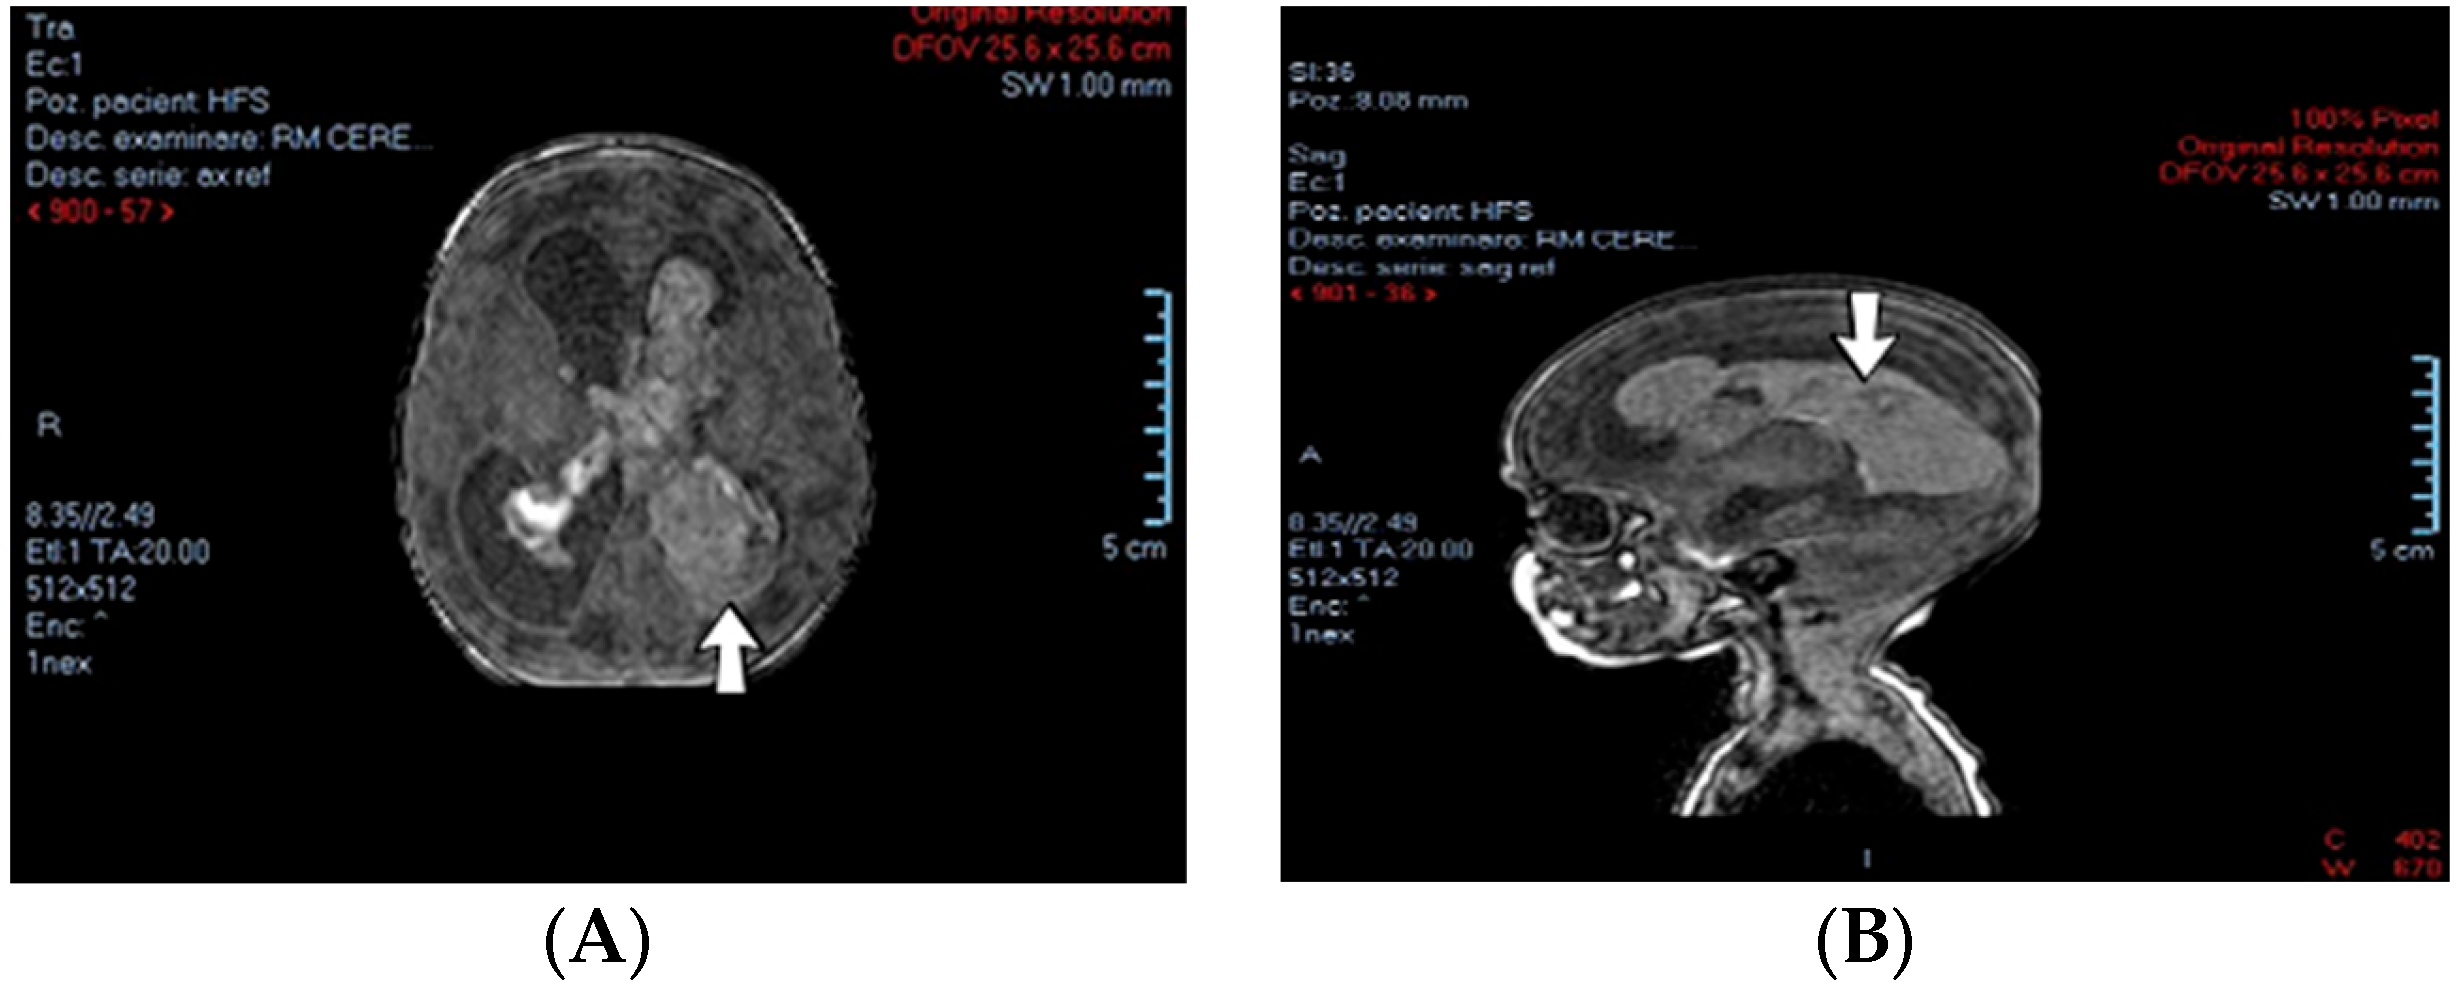

A 2-week-old female neonate (39 weeks, 3.16 kg) presented with opisthotonos and generalized tonic–clonic seizures, known with hydrocephalus of the lateral and third ventricles, from a consultation performed a couple of hours before admission. The brain ultrasound from admission indicated left intraventricular hemorrhage and intraparenchymal hemorrhage of the left parietal and occipital lobes, affecting the left thalamic and subthalamic regions, with extension to the right thalamus (Figure 3).

Figure 3.

Case no. 1. Left intraventricular hemorrhage on brain MRI—transverse (A) and sagittal (B) views.

A suspicion of postnatal stroke was raised, and genetic testing confirmed inherited thrombophilia, with positive MTHFR A1298C and Fibrinogen 455 G>A heterozygous gene mutations and Protein C deficiency. There was limited information about the family history.